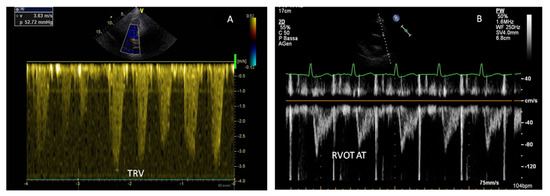

| PASP | The most used non-invasive tool for estimating PAP | PASP > 35 mmHg | |

| PAAT | Represents pulmonary flow acceleration, which increases as the vascular resistance is augmented | PAAT 136–153 ms | |